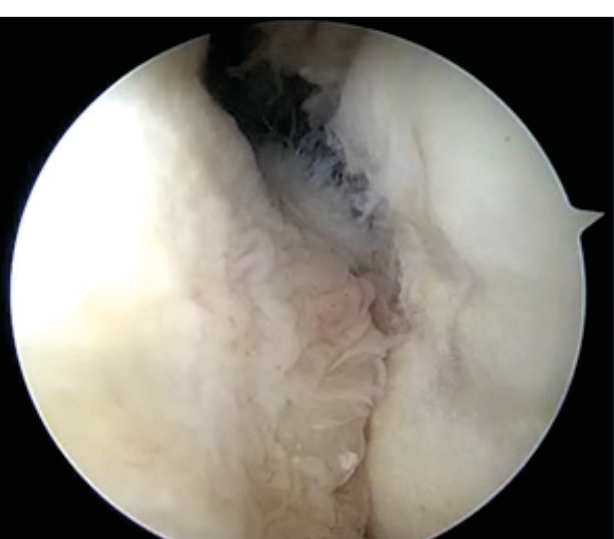

For combined arthroscopic bankart repair and remplissage, we start with diagnostic arthroscopy, followed by mobilization of Bankart's lesion and preparation of the glenoid. Inferior labral suture and a 5 0'clock anchor is placed. Remplissage procedure is then performed except knot tying. Once the Bankart's repair is completed, knot tying is done for remplissage. (Figure 12)